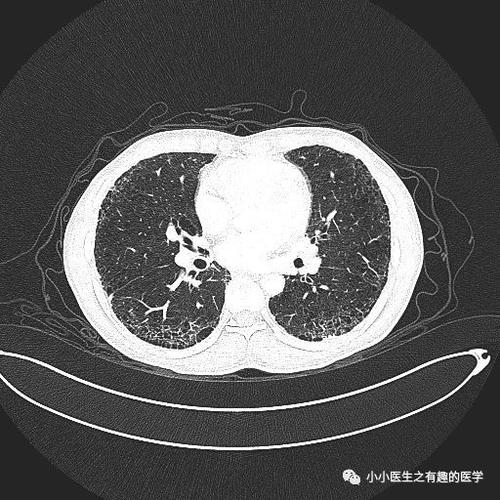

间质性肺炎ct图片

间质性肺炎ct图片,间质性肺炎ct图片特点

极易漏诊的间质性肺炎,从ct上怎么看?

间质性肺炎ct图片特点

间质性肺炎早期ct图片

间质性肺炎ct表现